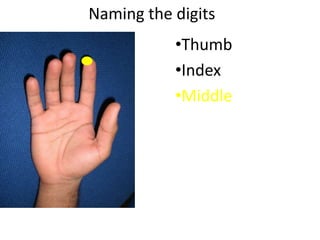

- Naming the bones, joints, tendons, nerves and skin landmarks of the hand and wrist.